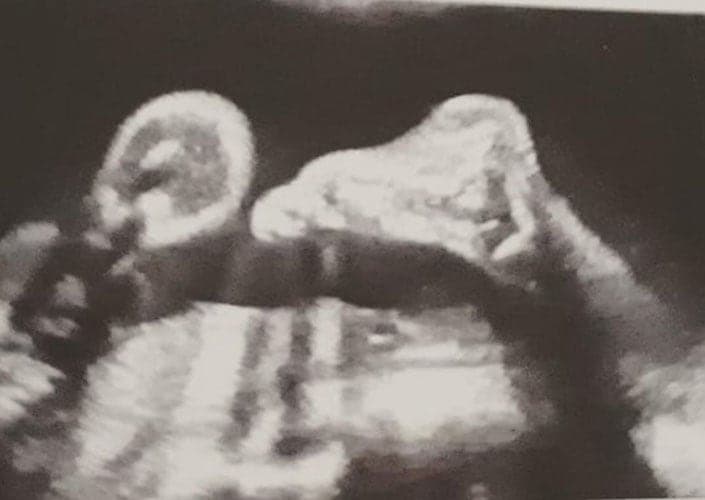

Ultraschallbilder aus dem 2. Trimester (13. bis 28. SSW)

Im 2. Trimester bekommt man oft die schönsten "Ganz-Körper" Ultraschallbilder. Das Baby ist nun so groß, dass man alles gut erkennen kann und noch nicht zu groß, so dass es noch ganz auf das Bild passt. In dieser Zeit lässt sich meist das Geschlecht bestimmen, wobei manche Babys es einfach nicht preis geben wollen und sich immer so drehen, dass man nichts erkennen kann.